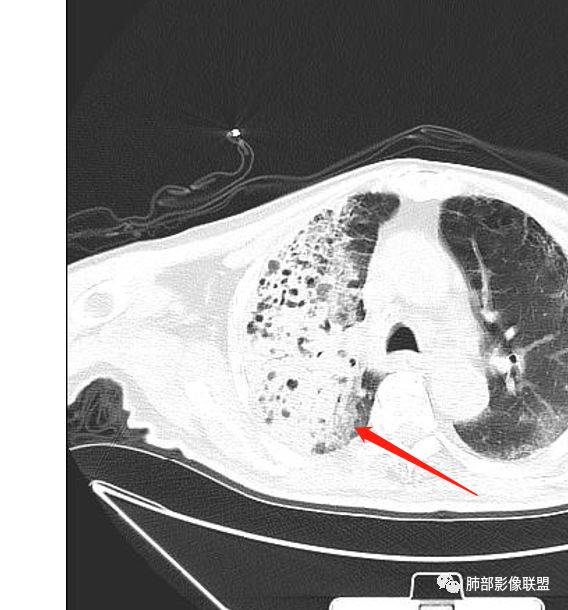

老年男性,糖尿病患者,右上肺大片实变,内可见多发虫蚀样空洞,右尖段近胸膜处一空洞内可见一类圆形结节影,支气管扩张,淋巴结肿大,双下肺索条,胸膜增厚。结合糖尿病病史,首选考虑结核干酪性肺炎合并曲霉菌感染,待排肺炎型肺癌

Shelia??:

老年男性,糖尿病10年,咳嗽气喘10天,肺气肿背景,右上肺大片实变影,内见虫蚀样空洞及空气支气管征,局部可见新月形空洞影,支气管局部欠光整,考虑感染性病变,结核?其内合并曲霉可能。

老年男性,糖尿病病史,咳嗽咳痰10余天入院。右上肺实变,见支气管充气征,部分支气管扩张,虫蚀样空洞,无壁空洞内壁光滑,实变病灶内见粘液成分,右上肺体积稍缩小,结核和肺炎性肺癌的鉴别,结核可能大,合并间质性肺病。

1、结核干酪空洞常很干净,很彻底,而粘液腺癌空洞内有液性成份,不干净。

2、支气管:干酪样肺炎内的支气管破坏的,扩张的,粘液腺癌小支气管多狭窄的堵塞的,大支气管较完好,枯枝征。